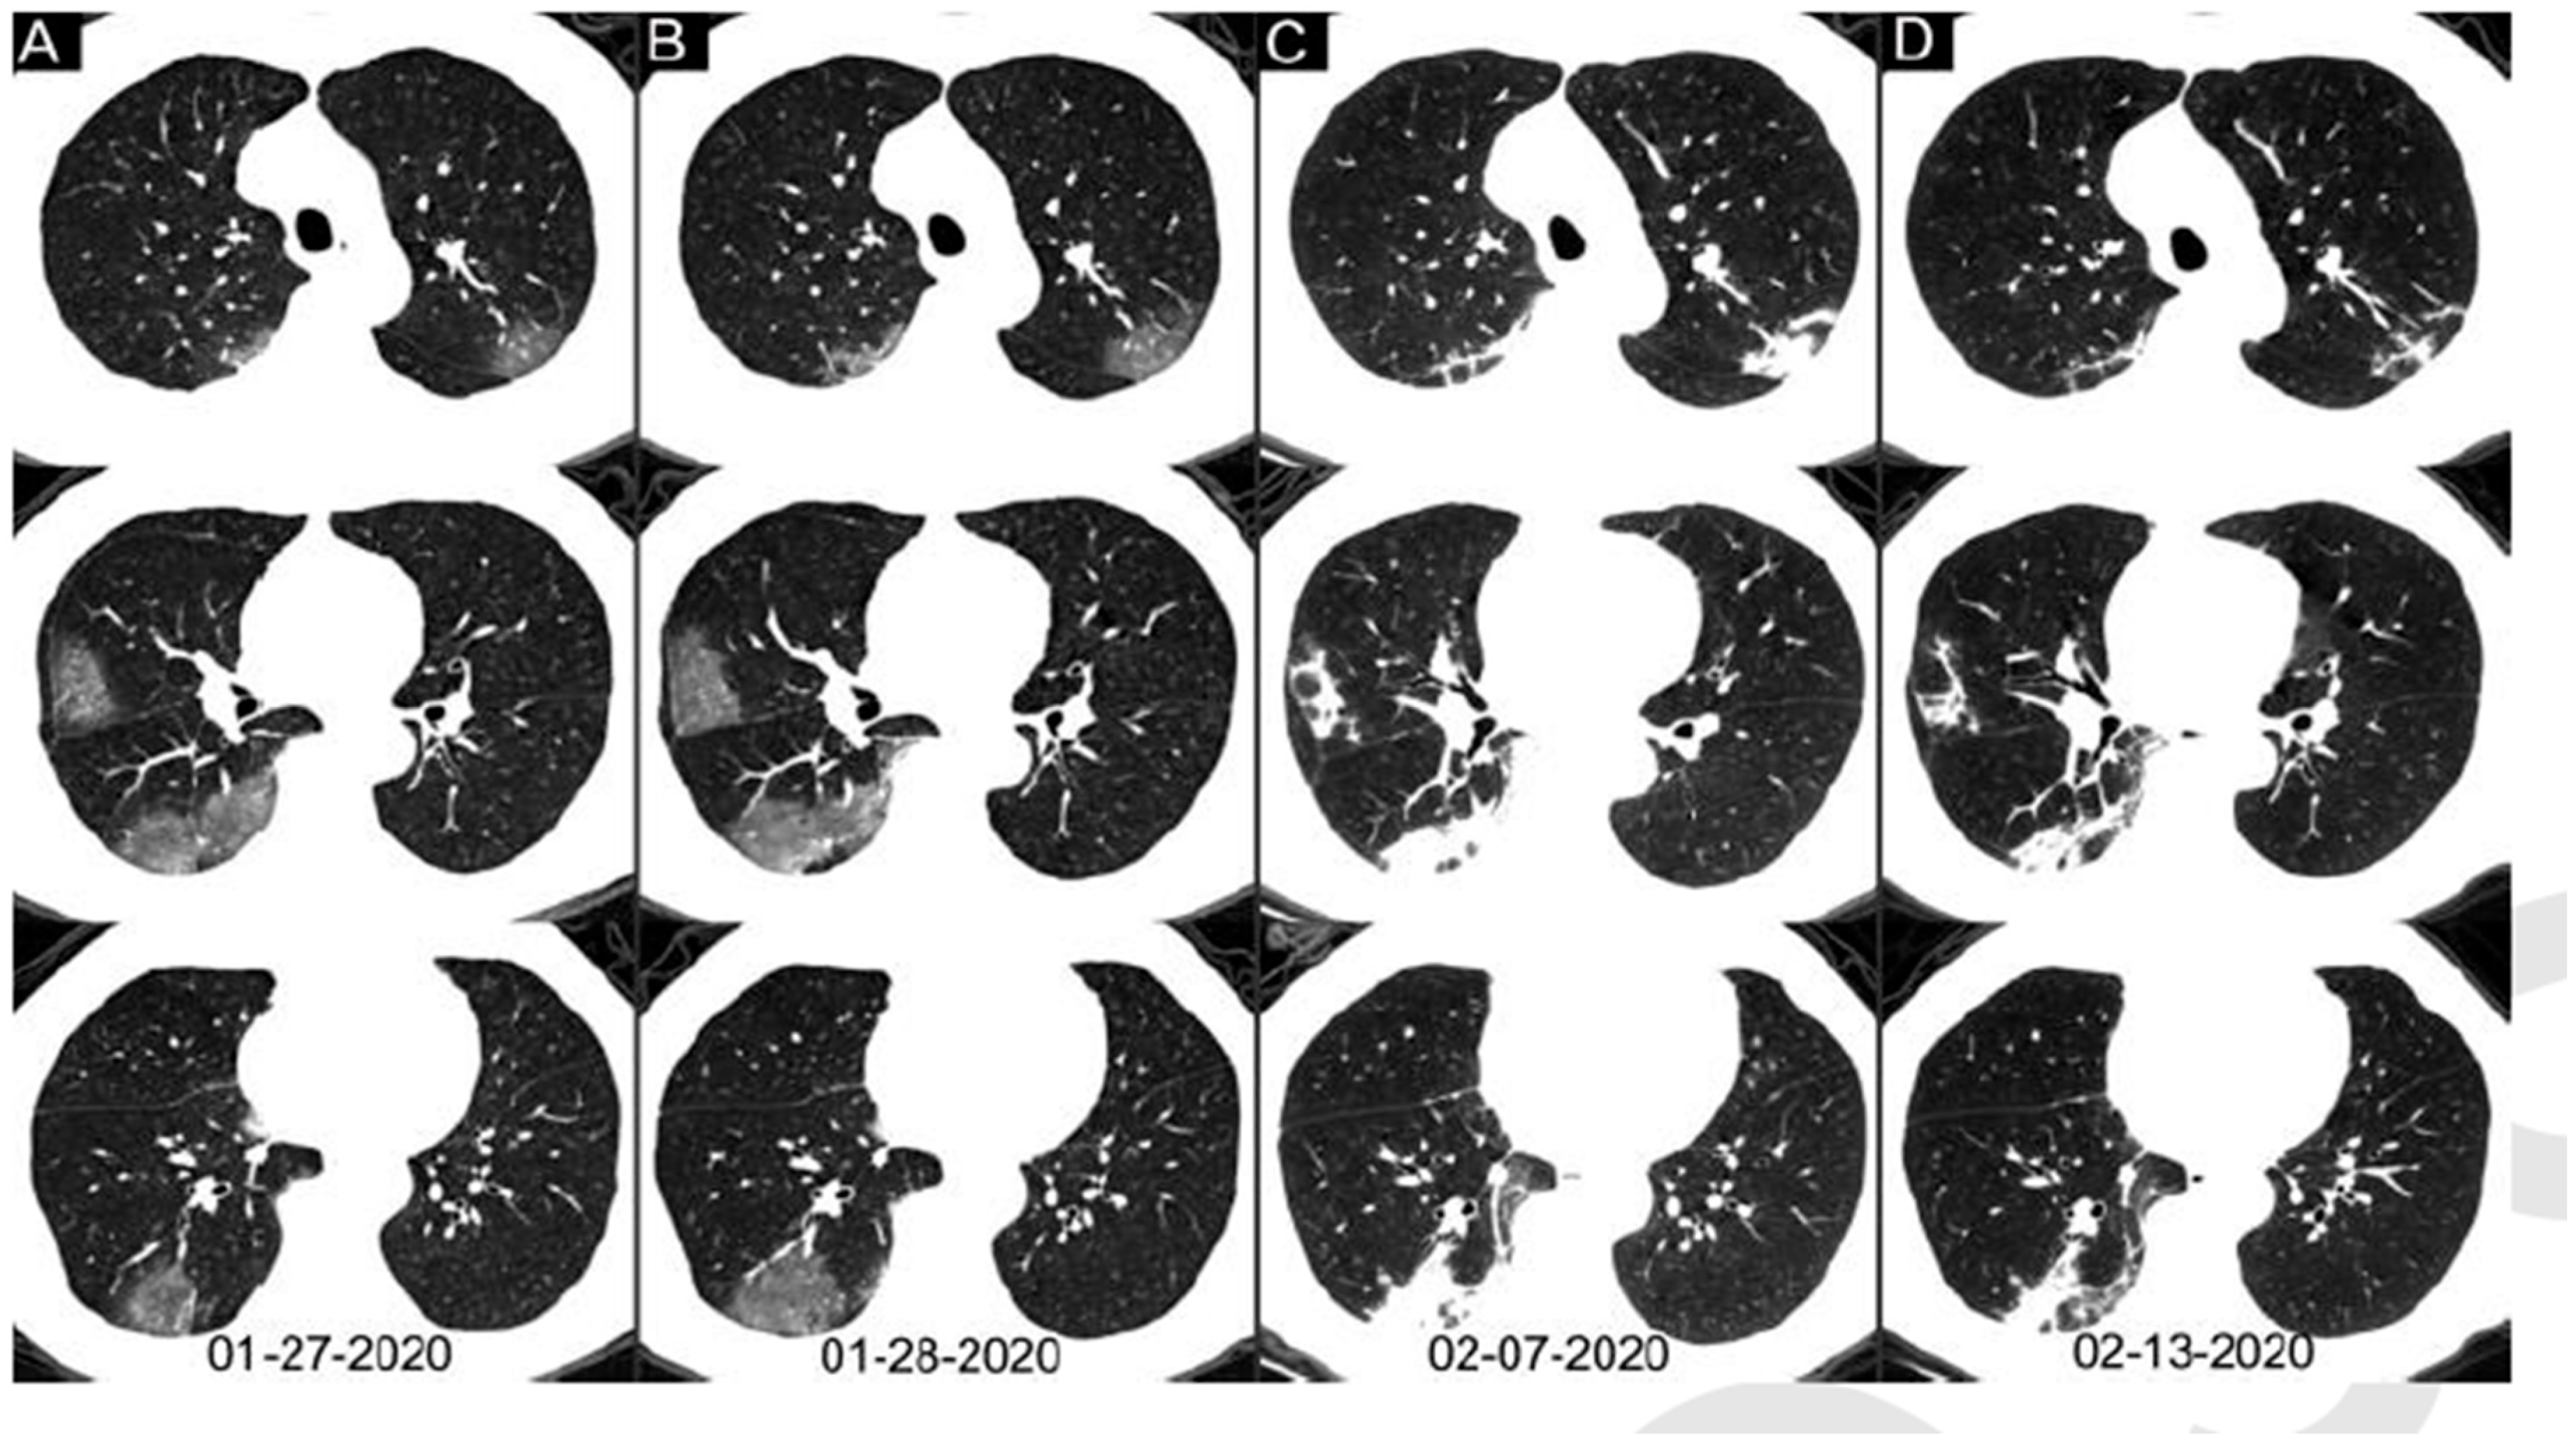

- Pan, F.; Ye, T.; Sun, P.; Gui, S.; Liang, B.; Li, L.; Zheng, D.; Wang, J.; Hesketh, R.L.; Yang, L.; et al. Time course of lung changes on chest CT during recovery from 2019 novel coronavirus (COVID-19) pneumonia. Radiology 2020, 295, 715–721. [Google Scholar] [CrossRef] [PubMed]

3.1. Case A